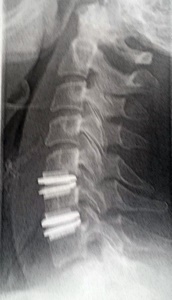

My Wife's ADR

History - November Of 2017 |

|

We traveled to Germany after

my wife was ruled

inoperable. Whereas, on

November 7, 2017 my Neurosurgeon implanted two

cervical ADRs in my wife's

neck as illustrated on the

right. Her surgery was

smooth as I had gotten my

wife to him quickly."